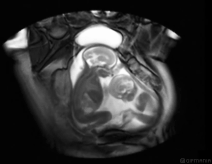

结婚一年的黄晓明夫妇,最近宣布造人成功。这对年龄相差11岁的艺人夫妇一直话题不断,去年隆重的婚礼才刚过去,杨颖的整容鉴定事件才刚平息,现在又传出怀孕的喜讯,人气持续攀升。而杨颖的怀孕,大家更将眼睛放到肚子里的宝宝,等待着验证杨颖和黄晓明出道以来未曾停止过的整容真相。